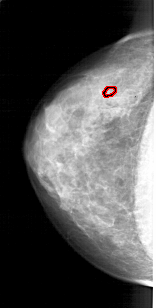

A_1914_1.LEFT_CC

LEFT_CC LINES 4306 PIXELS_PER_LINE 2176 BITS_PER_PIXEL 12 RESOLUTION 43.5 OVERLAY

FILE: A_1914_1.LEFT_CC.OVERLAY

TOTAL_ABNORMALITIES 1

ABNORMALITY 1

LESION_TYPE CALCIFICATION TYPE PLEOMORPHIC DISTRIBUTION CLUSTERED

ASSESSMENT 4

SUBTLETY 2

PATHOLOGY BENIGN

TOTAL_OUTLINES 1

BOUNDARY